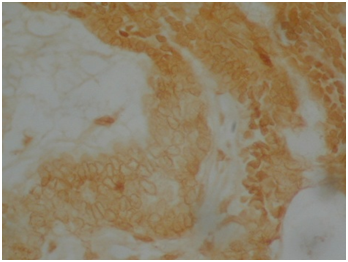

HMW cytokeratin was positive in all 22cases in all squamous parts (Figure 4). Cytokeratin 19 was positive in PBC and SR but negative in SMS and WK parts (Figure 5). Cytokeratin 20 was negative in all squamous parts. LMW cytokeratin: was positive in the PBCs and SMS but reduced in SR and negative in WK in 17/22cases (Figure 6). Cytokeratin 7 was positive in the SR but not in the PBC, SMS or WK in 19/22cases (Figure 7). Cytokeraitn 5/6 was positive in all three layers SMS, SR and PBC but negative in wet keratin in 22/22 cases (Figure 8).EMA was positive in SR and WK, but negative in PBC and SMS in 17/22cases (Figure 9).p63 was positive in PBC and SR cells, but negative in WK and SMS in 16/22cases (Figure 10).p16 was positive in PBC and SR in 15/22cases (Figure 11).Twelve cases show positive p53 immunostainings with range 2%-50% of the cells (Figure 12). Ki67 showed more than 10% positivity in 13cases (Figure 13) and low positivity or negative in 12cases. B-catenin was positive in PBC in 11cases in cytoplasmic and nuclear pattern and was positive in 11cases in cytoplasmic pattern only.

Figure 7 Cytokeratin 7 was positive in SR but not in SMS, PBC or WK cells.